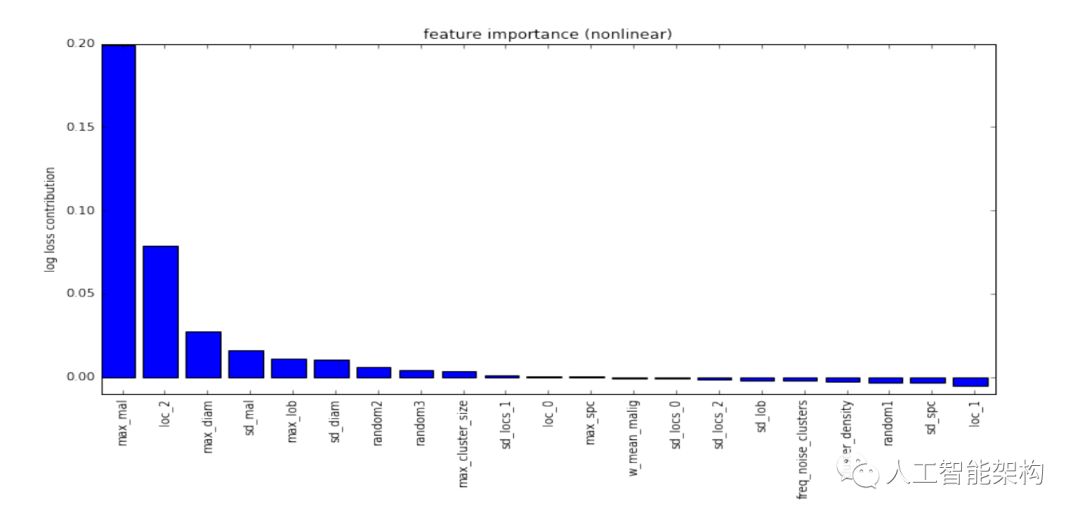

上图为特征重要性图。这18个特征被输入至“微小非线性”分类器中用于预测最终的诊断结果。分类器由L1-penalized逻辑回归模型组成以及一个极限随机树模型用于拟合线性模型的残差。附加特征——Julian的肿块(mass)检测模型的输出,用于预测患者肺部“异常肿块(mass)”的数量。